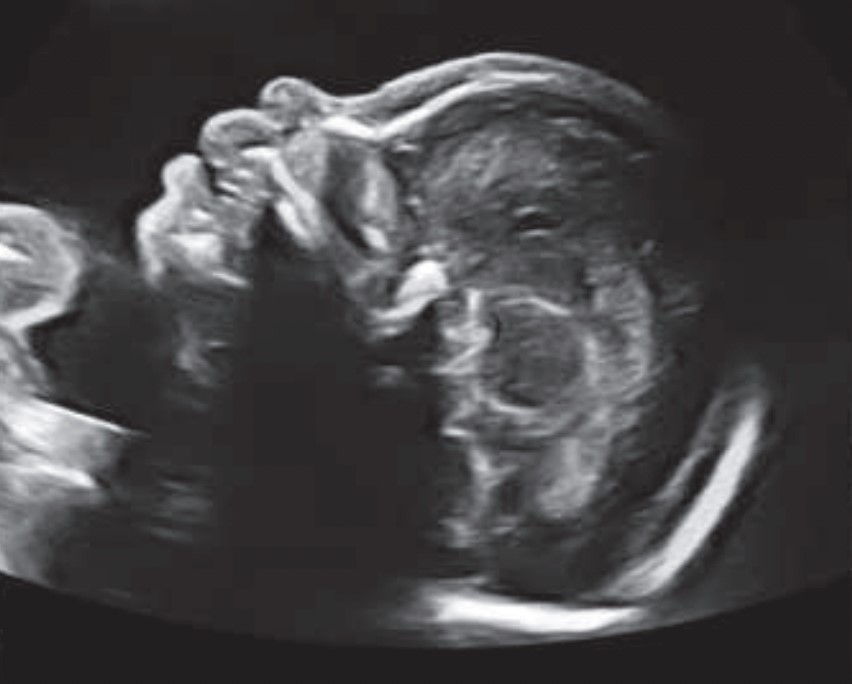

Ecografía de tamizaje genético: aunque puede realizarse entre las semanas 11 a 14, el mejor momento para hacer la ecografía de tamizaje genético es la semana 12. El tamaño actual del bebé permite determinar si la mayoría de órganos se estén desarrollando de manera adecuada. Esta ecografía en manos expertas puede detectar hasta el 60% de las malformaciones mayores que se pueden presentar durante el embarazo.

Uno de los parámetros más importante es la medición de la nuca del bebé conocida como translucencia nucal, que corresponde al líquido que todos los fetos tienen en la parte posterior del cuello. El grosor de la nuca del feto se utiliza para establecer el riesgo de síndrome de Down. Para calcular este riesgo se combina la medida de la nuca con tu edad, la presencia de soplo en el corazón, la forma en que palpita una vena que llega al corazón conocida como ductus venoso y los valores de dos hormonas (BHCG y PAPP-A) que se obtienen mediante una muestra de tu sangre.

Esta ecografía también permite establecer el riesgo de otras posibles complicaciones del embarazo como el parto prematuro, la preeclampsia (presión alta durante el embarazo) y la restricción del crecimiento fetal (bajo peso del bebe durante la gestación). En caso de identificar alto riesgo de preeclampsia tu médico te formulará 150 mg de ácido acetil salicílico cada noche y calcio para disminuir la probabilidad de que esto ocurra.